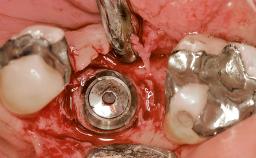

Early Placement of an Implant in a Maxillary Right Central Incisor Site

This 41-year-old female patient was referred to the clinic for the replacement of the right central incisor, since the tooth had developed a root fracture in the long axis that made extraction necessary. The healthy, non-smoking patient was first seen with the tooth still in place. A detailed Esthetic Risk Assessment was performed.The patient was worried about her dental esthetics and had high expectations for a successful treatment outcome from an esthetic point of view. The patient had a medium lip line that displayed parts of the gingiva in the anterior maxilla upon smile.

Type of Implants Two-Piece

Bone Augmentation Horizontal|Simultaneous

Augmentation Materials Autogenous chips|Xenogenous|Membrane

Bone Volume Deficient horizontally, allowing simultaneous augumentation